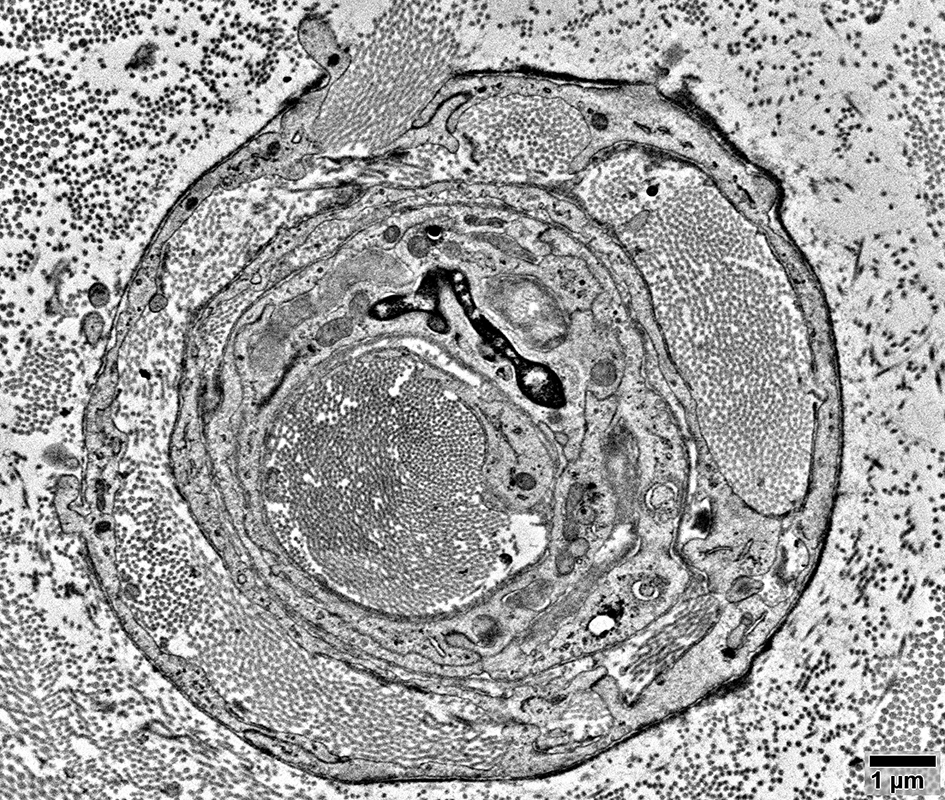

Pseudo-Onion bulbs, Incompletely formed

Schwann cell processes: Multiple; Complex structure

Axons: Varied myelination

Pseudo-Onion bulbs, Complex

Myelinated axons surrounded by non-myelinating Schwann cells